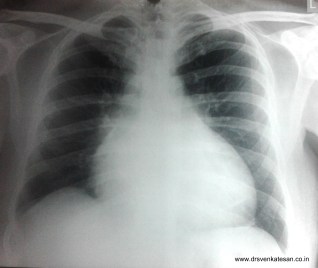

Here is a patient with class 3  dyspnea  who was referred  for echocardiography

X ray chest showing cardiomegaly